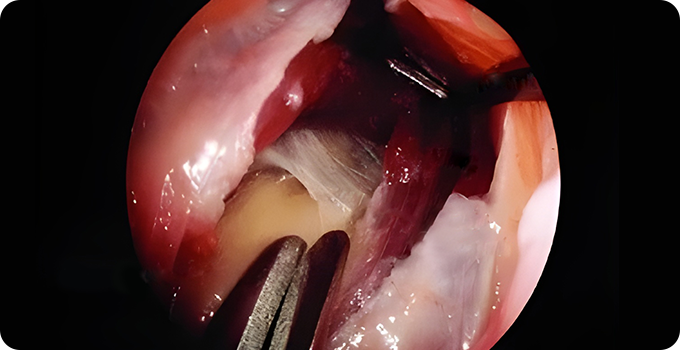

신경 감압술

팔꿈치 터널증후군의 내시경적 신경감압술은 최소 침습적 방법으로 척골신경의 압박을 완화하는 수술입니다. 관절경을 사용하여 신경을 압박하는 구조물을 제거하거나, 신경을 새로운 위치로 이동시켜 압박을 줄이는 방식으로 진행됩니다. 이 방법은 절개 부위가 작아 흉터가 적고 회복이 빠르며, 전신마취 없이도 시행 가능합니다.